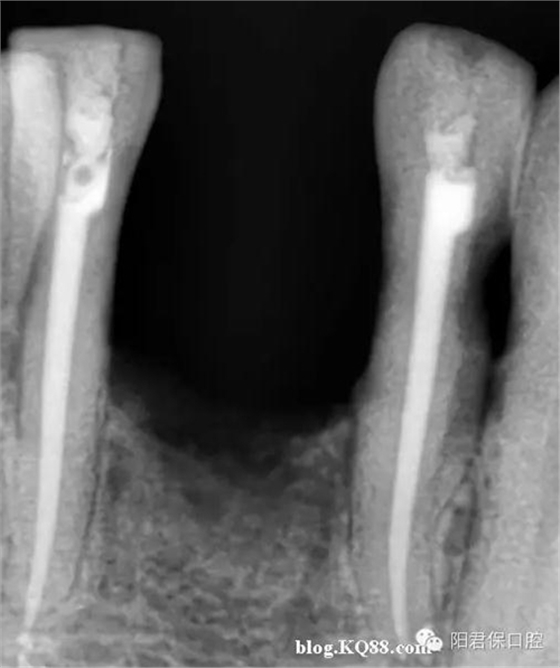

患者:姜XX 性別;女 年齡:65 根據(jù)齲壞程度、患者的癥狀、修復需要,且對收費及牙髓處理均征得同意后第一次行右下4、5,左下4、5、6;第二次行左下2,右下2 ,右上7一次性根管治療術(shù)。

術(shù)后見右下4,左下4均有側(cè)支充填,且位置對稱,左下6近中根中部有側(cè)支;左下5、左下6遠中根管均多個開口。

熱牙膠垂直加壓后有封閉劑和牙膠超填,但無術(shù)后反應。